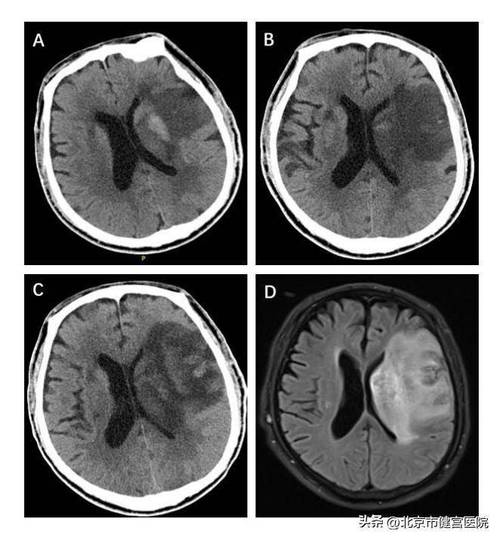

在脑梗死的超急性期(发病后24小时内)常规CT平扫通常显示为阴性,即看起来“正常”,这是脑CT在诊断早期脑梗死时最主要的局限性,有经验的放射科和临床医生能够通过寻找一些早期间接征象来高度怀疑脑梗死,并利用CT血管成像来明确病因。

第二阶段:发病后6-24小时

随着缺血时间的延长,细胞水肿加剧,并开始出现血管源性水肿,一些早期征象会变得更加明显。

• 常规CT平扫表现:

• 脑实质密度降低:这是梗死核心区开始出现不可逆损伤的标志,缺血区域的脑组织因为细胞崩解、水肿和蛋白质分解,密度开始逐渐低于周围正常脑组织,但在24小时内,这种密度差异通常仍然很轻微,不仔细观察容易漏诊。

• 占位效应开始显现:随着水肿范围的扩大,梗死区域可能出现轻微的脑室受压中线结构轻度移位,但大面积梗死导致的明显中线移位通常在24小时之后才会出现。

• 岛带消失征:这是大脑中动脉供血区梗死的另一个高度特异性早期征象,岛叶(脑岛)的皮层密度通常比邻近的额叶和顶叶皮层略高,当大脑中动脉闭塞导致岛叶缺血时,其密度会迅速降低,与周围皮层密度变得一致,形成“消失”的假象,这个征象在发病后6-12小时左右出现率较高。